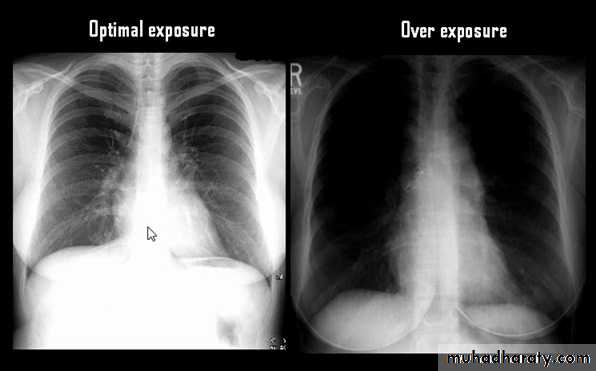

Routine Examination includes

P-A view , Other supplementary views are done according to the case. So all Patients admitted to hospital should have P-A X-ray In standing erect view in complete inspiration